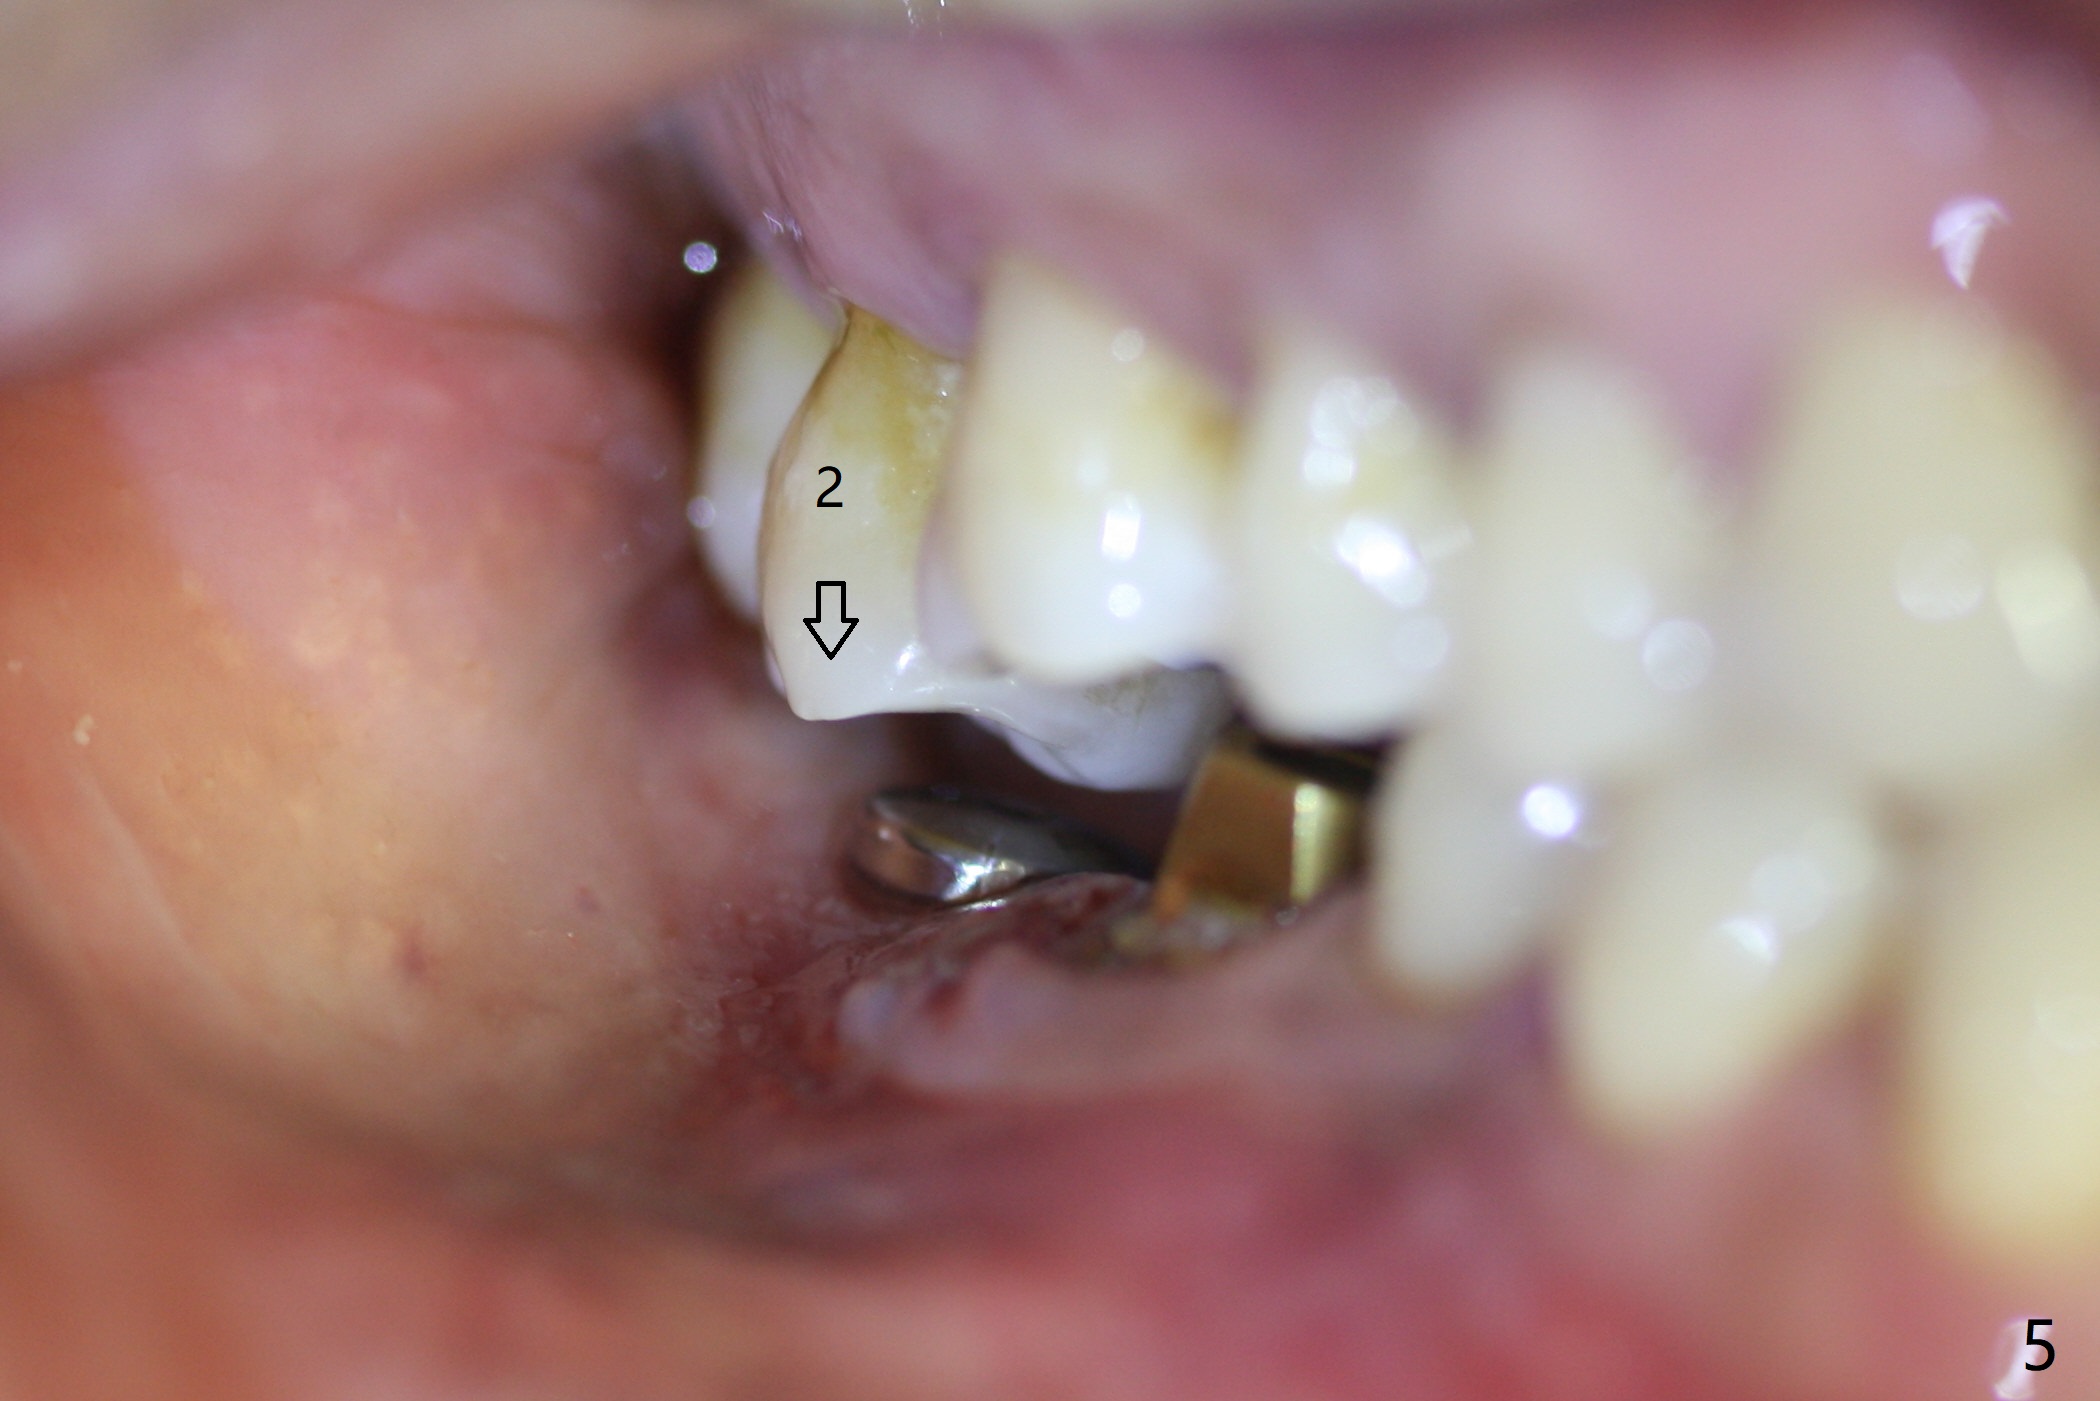

Abutment vs. Definitive One

After extraction of the tooth #30 with lingual subgingival fracture (Fig.1), the septum is fairly large (Fig.2 S). A bony vertical anchor pin (Fig.3 *) is inserted in the septum following pointed drill to to stabilize the guide during osteotomy and implant placement of #31. When the latter is finished, a fixture anchor pin is used at #31 as planned. A healing abutment is placed at #31 because of supraeruption of the tooth #2 (Fig.4,5), while a cementation abutment is placed at #30 (Fig.5) with autogenous bone (from drills) and allograft placed around it (*, Fig.6). Finally an immediate nonfunctional provisional is fabricated to keep the bone graft in place (Fig.7 P). The bone graft remains in place gel-like nearly 1 month postop (Fig.8). CBCT axial section shows that there is not enough space for mini implant placement at the tooth #2 (Fig.9). Restoration-induced intrusion will be conducted using the implants at #30 and 31 three-4 months postop. The buccal gingiva (Fig.10 *) is lingual to the provisional (P) nearly 1.5 months postop. When the provisional is removed, it appears that the mesiobuccal bone graft has lost (Fig.11). Two days later, the cementation abutment is loose and removed; the gingival cuff looks healthy (Fig.12). A 6.8x5 mm healing abutment is placed (Fig.13). In 2.5 to 3 months, abutments will be placed at #30 and 31. Splinted provisional will be fabricated over supraocclusion to intrude the tooth #2 with a stop on the left side. Surprisingly the patient agrees to intrude the tooth #2 with 2 mini implants 5.5 months postop (Fig.14,15). However, the miniimplants dislodged. Due to coronavirus, the implants are restored with heavy abutment and opposing tooth trimming 1 year 9 months postop (Fig.16). Magicore should have been placed instead.